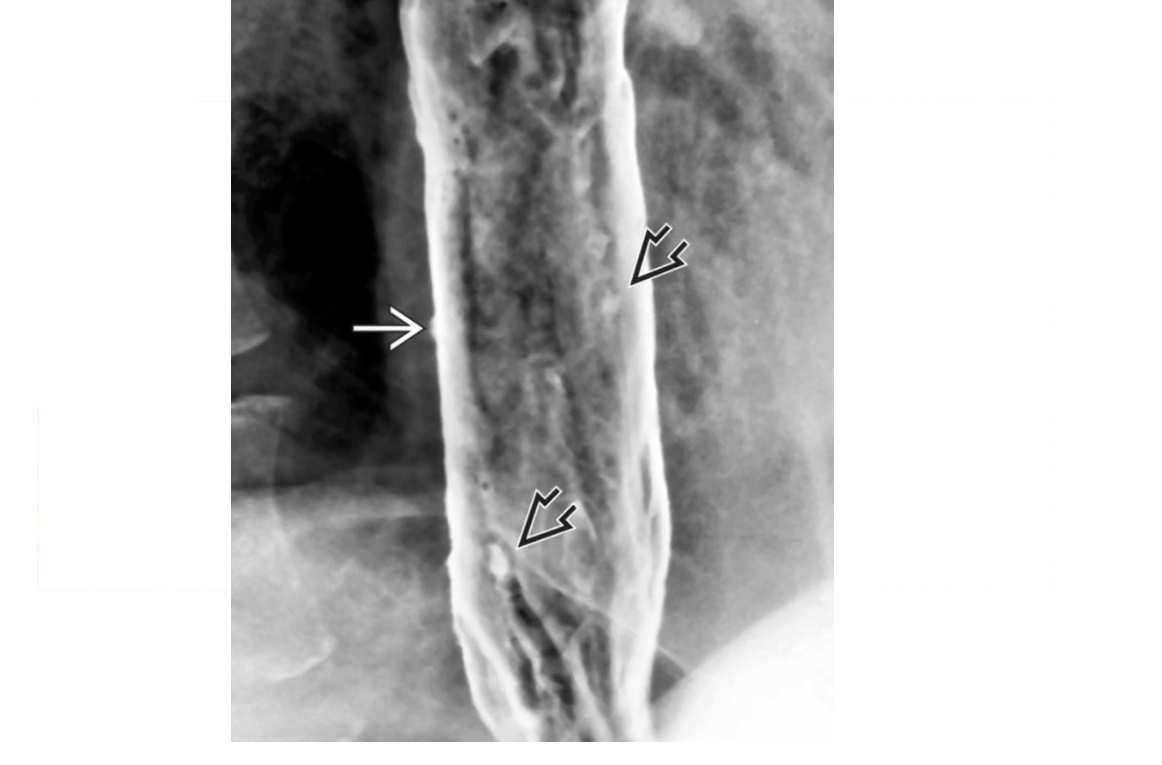

Oesophageal pseudodiverticulosis

Barium - multiple, tiny (1- to 4-mm depth), flask-like outpouchings in the oesophagus

Barium trapped in dilated excretory ducts of submucosal glands

CHRONIC REFLUX* and Candida